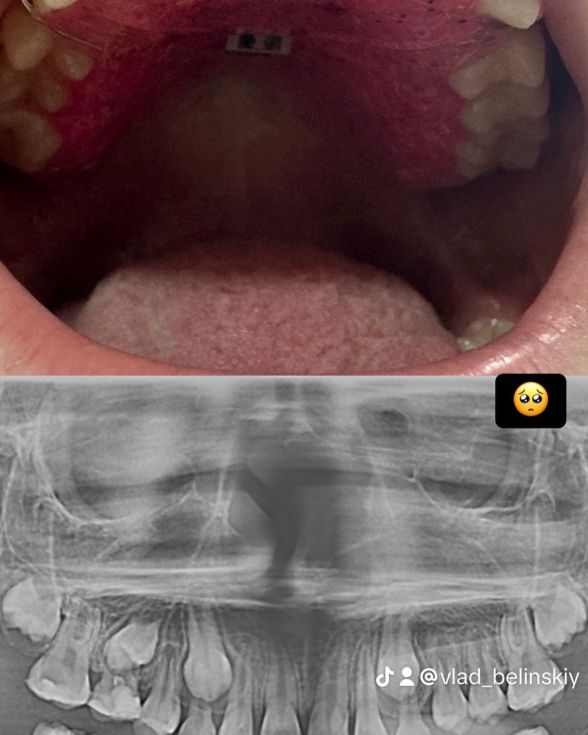

Стоматолог-ортодонт Белінський Владислав

Стоматолог-ортодонт Владислав Андрійович Белінський – це спеціаліст, який надає кваліфіковану стоматологічну допомогу дітям, орієнтуючись на сучасні стандарти якості та безболісне лікування. Він приділяє особливу увагу кожному маленькому пацієнту, створюючи комфортну атмосферу і забезпечуючи ефективне лікування без стресу для дитини.

Лікар-ортодонт допомагає у вирішенні проблем із прикусом та неправильним розміщенням зубів, що є дуже важливим у дитячому віці для формування здорової зубної архітектури в майбутньому. Владислав Андрійович використовує інноваційні методи та сучасні технології для досягнення найкращих результатів.

TikTik @vlad_belinskiy